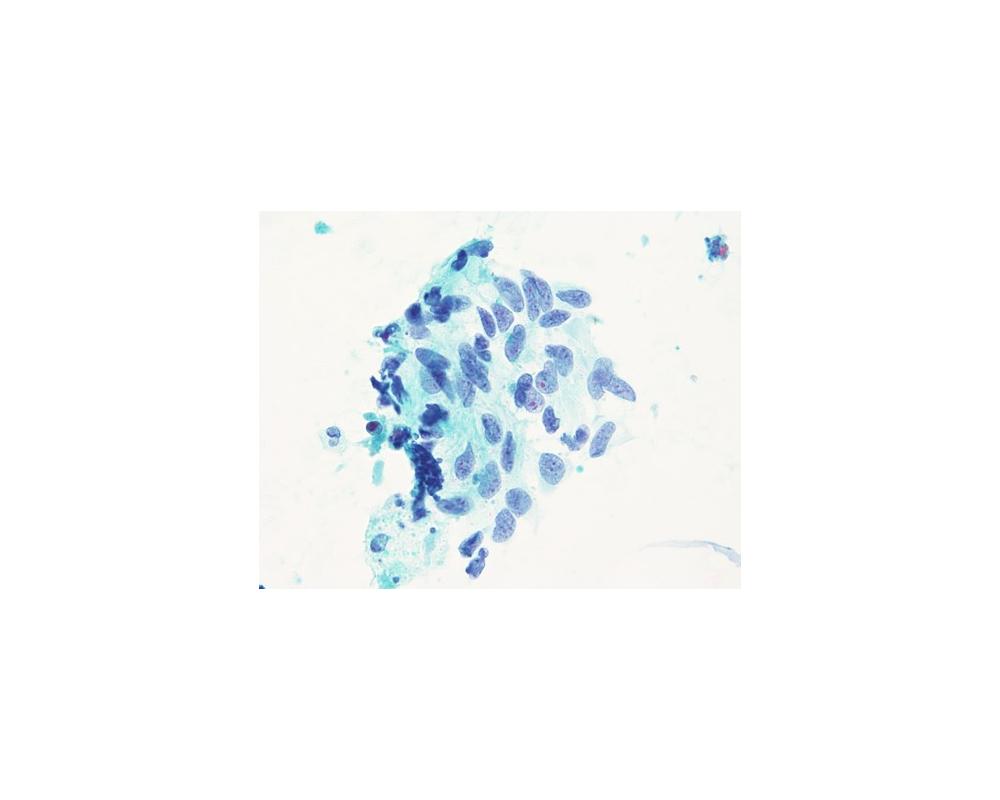

第40回日本臨床細胞学会九州連合会学会(大分)スライドカンファレンス症例4

種別:甲状腺

出題:松岡 優毅1、中島 正洋1,2 1長崎大学病院 病理診断科・病理部、2長崎大学原爆後障害医療研究所 腫瘍・診断病理学研究分野

| 年齢 | 80代 | 性別 | 女性 |

| 採取部位 | 甲状腺 | 採取方法 | 穿刺吸引細胞診 |

| 検体処理法 | ふきつけ |

既往歴・家族歴: なし

現病歴: 3か月前に7cm大の嚢胞性病変が指摘され穿刺吸引細胞診(Class III).増大、嗄声が確認され、再度穿刺吸引細胞診が施行された。なお、CT上では甲状腺から外方向性発育を示していた。採血データはThyroglobulinが84.3ng/mL(正常35.0以下)で、TSH、free T4、抗Tg抗体、抗TPO抗体は正常範囲内であった。

| 正解 | 4.Teratocarcinosarcoma |

▼選択肢及び投票結果

| 1.Adenomatous goiter | 10件 | (9.5%) | |

| 2.Papillary carcinoma | 27件 | (25.7%) | |

| 3.Intrathyroid thymic carcinoma | 48件 | (45.7%) | |

| 4.Teratocarcinosarcoma | 15件 | (14.3%) | |

| 5.Follicular neoplasm | 5件 | (4.8%) | |

| 投票総数 | 105件 | (100%) |